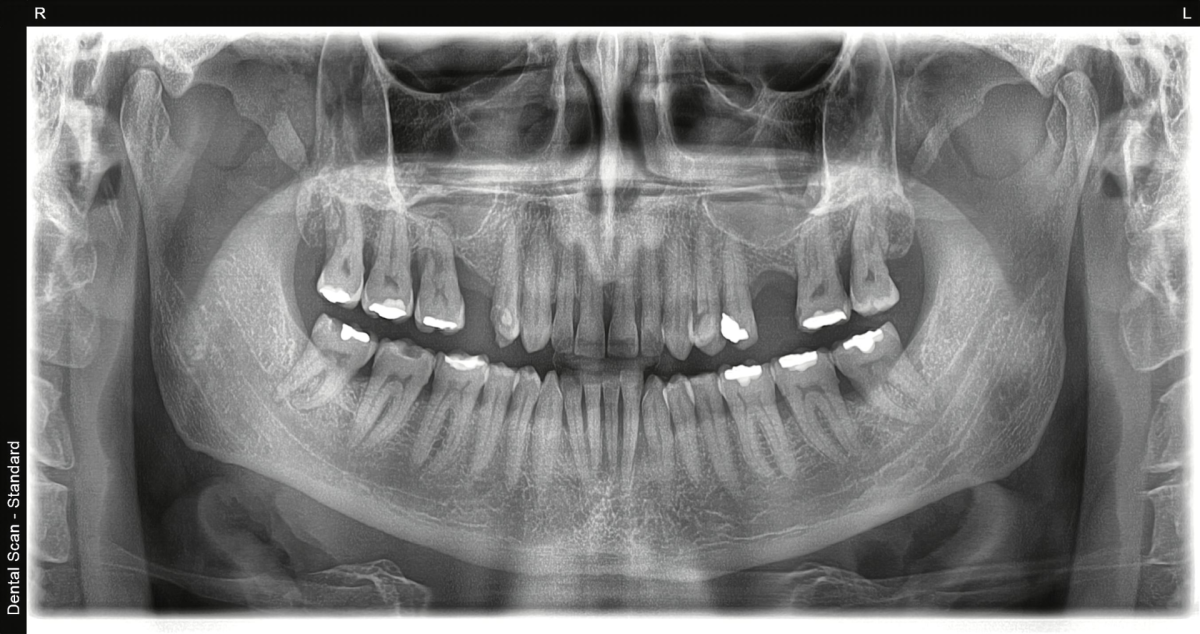

Digitalni rendgenski snimci

Savremeni digitalni sistemi omogućavaju brže dobijanje snimka, bolji kvalitet slike i nižu dozu zračenja u odnosu na starije analogne metode, uz to ortopan cena snimka je i dalje pristupačna.

U našem centru za snimanje zuba, digitalni ortopan snimak se izrađuje uz minimalnu dozu zračenja i maksimalnu dijagnostičku preciznost.

Kako izgleda snimanje?

Snimanje ortopana je jednostavno i traje svega nekoliko minuta. Pacijent stoji ili sedi u aparatu, glava se postavlja u pravilan položaj, a uređaj kruži oko glave i pravi panoramski snimak obe vilice. Tokom samog snimanja važno je da pacijent bude miran kako bi snimak bio što jasniji.

Procedura je brza, bezbolna i ne zahteva poseban oporavak nakon snimanja.